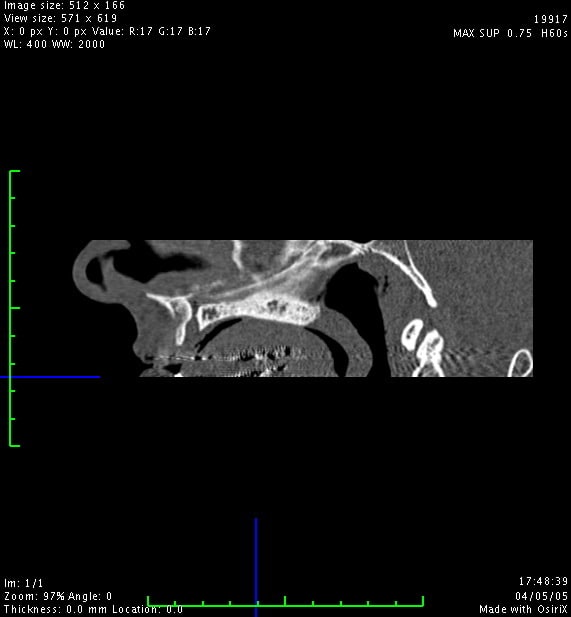

Je viens de revoir un jeune homme que j'ai dépanné en urgence cet été, suite à un problème infectieux récidivant sur sa 11.

De retour de vacances, son praticien a finalement extrait cette dent et l'a adressé à un stomato pour une éventuelle implantation, mais à la vue du scan (et selon mon patient) ce dernier n'est pas chaud pour une greffe. (proximité du canal palatin)

Voici quelques images, qu'en pensez-vous?

fais un scan avec des coupes coronales tu verras bien

vu ta coupe reconstituée, tu auras surement plus d'os a la symphyse qu'au ramus mais la encore, le scan préop est hyper important pour estimer ton site donneur

4/ le canal naso palatin n'est pas un probleme du tout, Chicot a mille fois raisons,il te suffit de virer son contenu et le remplacer par un bio mat ou mieux de l'autogene et tu oublies les craintes infondées du stomato; dans ce canal pas grand chose d'inquiétant ou de dangereux et tu gagneras en vestibulolingual.

A mon sens tu auras certainement à faire une greffe de conjonctif enfoui pour récupérer de l'épaisseur gingivale ainsi que des papilles ceci au vu de l'image 3D mais tu n'as pas pris de photos en bouche et il est délicat de confirmer ce deuxième temps.